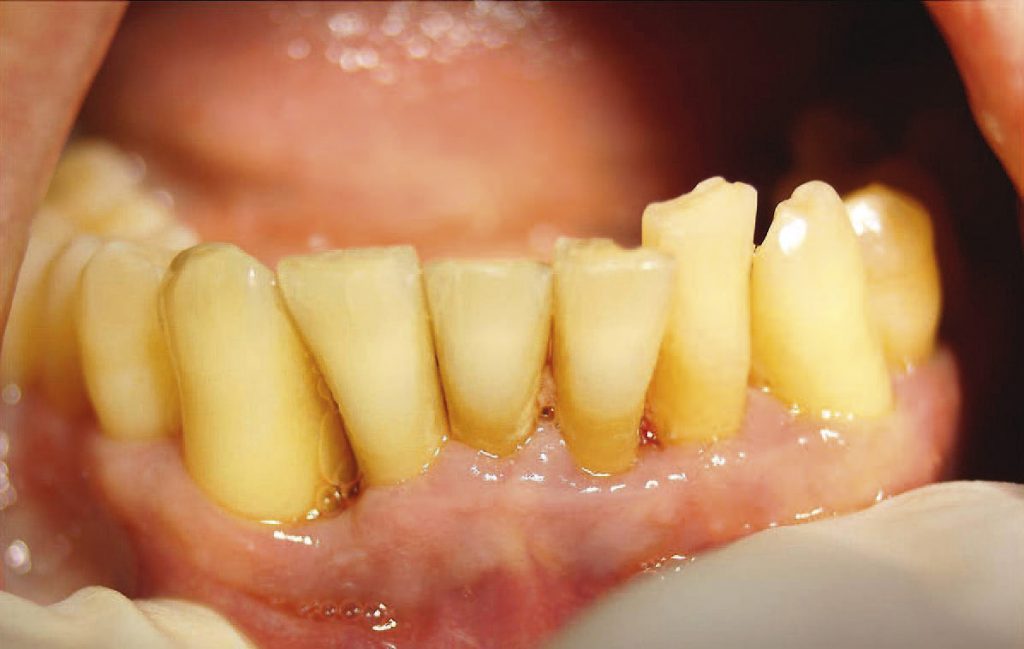

- Opis przypadku: Do Gabinetu Stomatologicznego Renata i Dariusz Paliga zgłosił się 56-letni pacjent z powodu przewlekłej uogólnionej zaawansowanej periodontopatii.